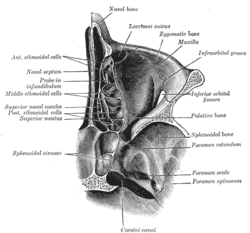

Coronal section of nasal cavities.

Coronal section of nasal cavities. Front of nasal part of pharynx, as seen with the laryngoscope.